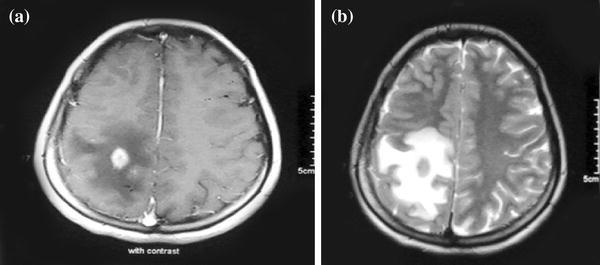

Upon examination, the patient was afebrile, and neurological examination showed left hemiparesis. Routine laboratory analyses indicated only leukocytosis (19,500/mm3). The differential blood count indicated 85.6% neutrophils and 4.8% lymphocytes. The C-reactive protein (CRP) value (40 mg/dl) and sedimentation rate (38 mm/h) were elevated. An initial serological titer for Brucella was positive at 1:640 via Wright’s agglutination test. Then, blood cultures were sent for Brucella. Magnetic resonance imaging (MRI) showed a 1.5 × 1.5 cm enhancing nodular lesion with moderate surrounding edema in the right parietal lobe (Fig. 1). These findings suggested a cerebral tumor. The patient underwent a right parietal craniotomy with the total excision of the neoplasm. The final examination of the pathological specimens showed a nongranulomatous encephalitis that consisted of diffuse lymphocytic infiltrates and perivascular lymphocytic cuffing (Fig. 2). The stains for mycobacteria, bacteria, fungi, and spirochetes were negative. These observations led us to investigate the etiology of encephalitis. Then, a lumbar puncture was performed. Examination of the CSF showed no pleocytosis, a protein concentration of 48 mg/dl, and a glucose level of 52 mg/dl. CSF samples were sent for Gram and Ziehl-Neelsen staining and bacterial, mycobacterial, and fungal cultures. Polymerase chain reaction (PCR) testing for Mycobacterium tuberculosis was performed as well. All results, as well as those of the CSF serologies for cytomegalovirus (CMV), Epstein–Barr virus (EBV), herpes simplex virus type 1 and 2 (HSV-1 and HSV-2), rubella, and toxoplasmosis, were negative. Serum serologies for human immunodeficiency virus, serum hepatitis C, CMV, EBV, HSV-1 and HSV-2, rubella, Borrelia burgdorferi, toxoplasmosis, and syphilis, except for serum hepatitis B, were negative. Wright’s agglutination test in the CSF was positive at 1:320 titers. Eventually, Brucella melitensis was isolated in the blood culture. Based on these findings, the patient was diagnosed with neurobrucellosis, presenting as nongranulomatous encephalitis. Therapy with rifampin (600 mg/day), trimethoprim–sulfamethoxazole (640–3,200 mg/day), and ceftriaxone (2 g/day) was started and continued for 3 weeks. Thereafter, therapy with rifampin (600 mg/day) and trimethoprim–sulfamethoxazole (640–3,200 mg/day) was maintained, but ceftriaxone was replaced with doxycycline (200 mg/day), and the new antimicrobial combination was planned to be continued for 6 months. On hospital day 14, the patient’s symptoms had apparently subsided. During the next 6 months, the patient will be followed up closely with serological, microbiological, and MRI imaging assays until complete recovery.

Fig. 1.

a Axial T1-weighted gadolinium-enhanced image shows a strongly enhancing 1.5 × 1.5 cm nodule in the right parietal cortex surrounded by vasogenic edema. b Axial T2-weighted image demonstrates vasogenic edema surrounding a low-signal central nodule

The differential diagnosis of a mass-occupying lesion with enhancement after the administration of a contrast agent is a brain tumor or abscesses [7]. In our patient, MRI imaging revealed an enhanced lesion with vasogenic edema in the right parietal lobe, interpreted as a cerebral tumor.